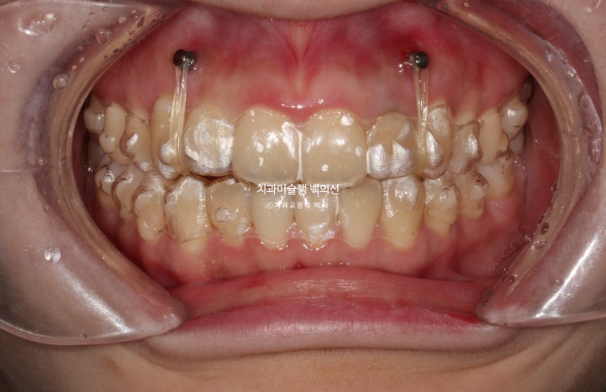

24.08

30개 장치를 1월부터 10월까지 10개월간 낀 모습입니다.

24.10

앞니 배열은 좋아졌지만 중심선이 아직 아쉽고 앞니 높낮이 단차의 개선이 좀더 필요합니다.

어금니 교합은 좋습니다.

배열도 대부분 완료되었습니다.